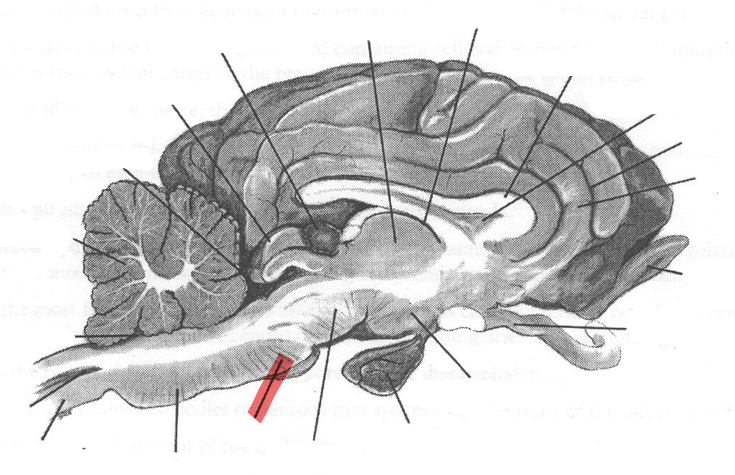

Identify highlighted arrow

Pons